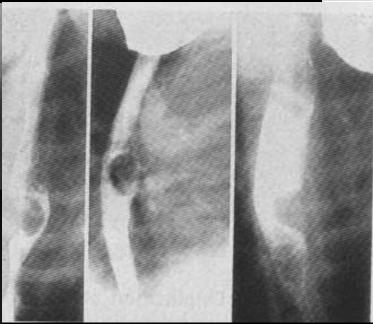

Image

radiologique de deux type de stenose oesophgienne

congenitale 1a, 2 et 1b en fusiforme , en flammeche

et abrupte |

|

Stenose

congenitale oesophagienne avec oesophagite

peptique(RGO). Oesophage en achalasia . |